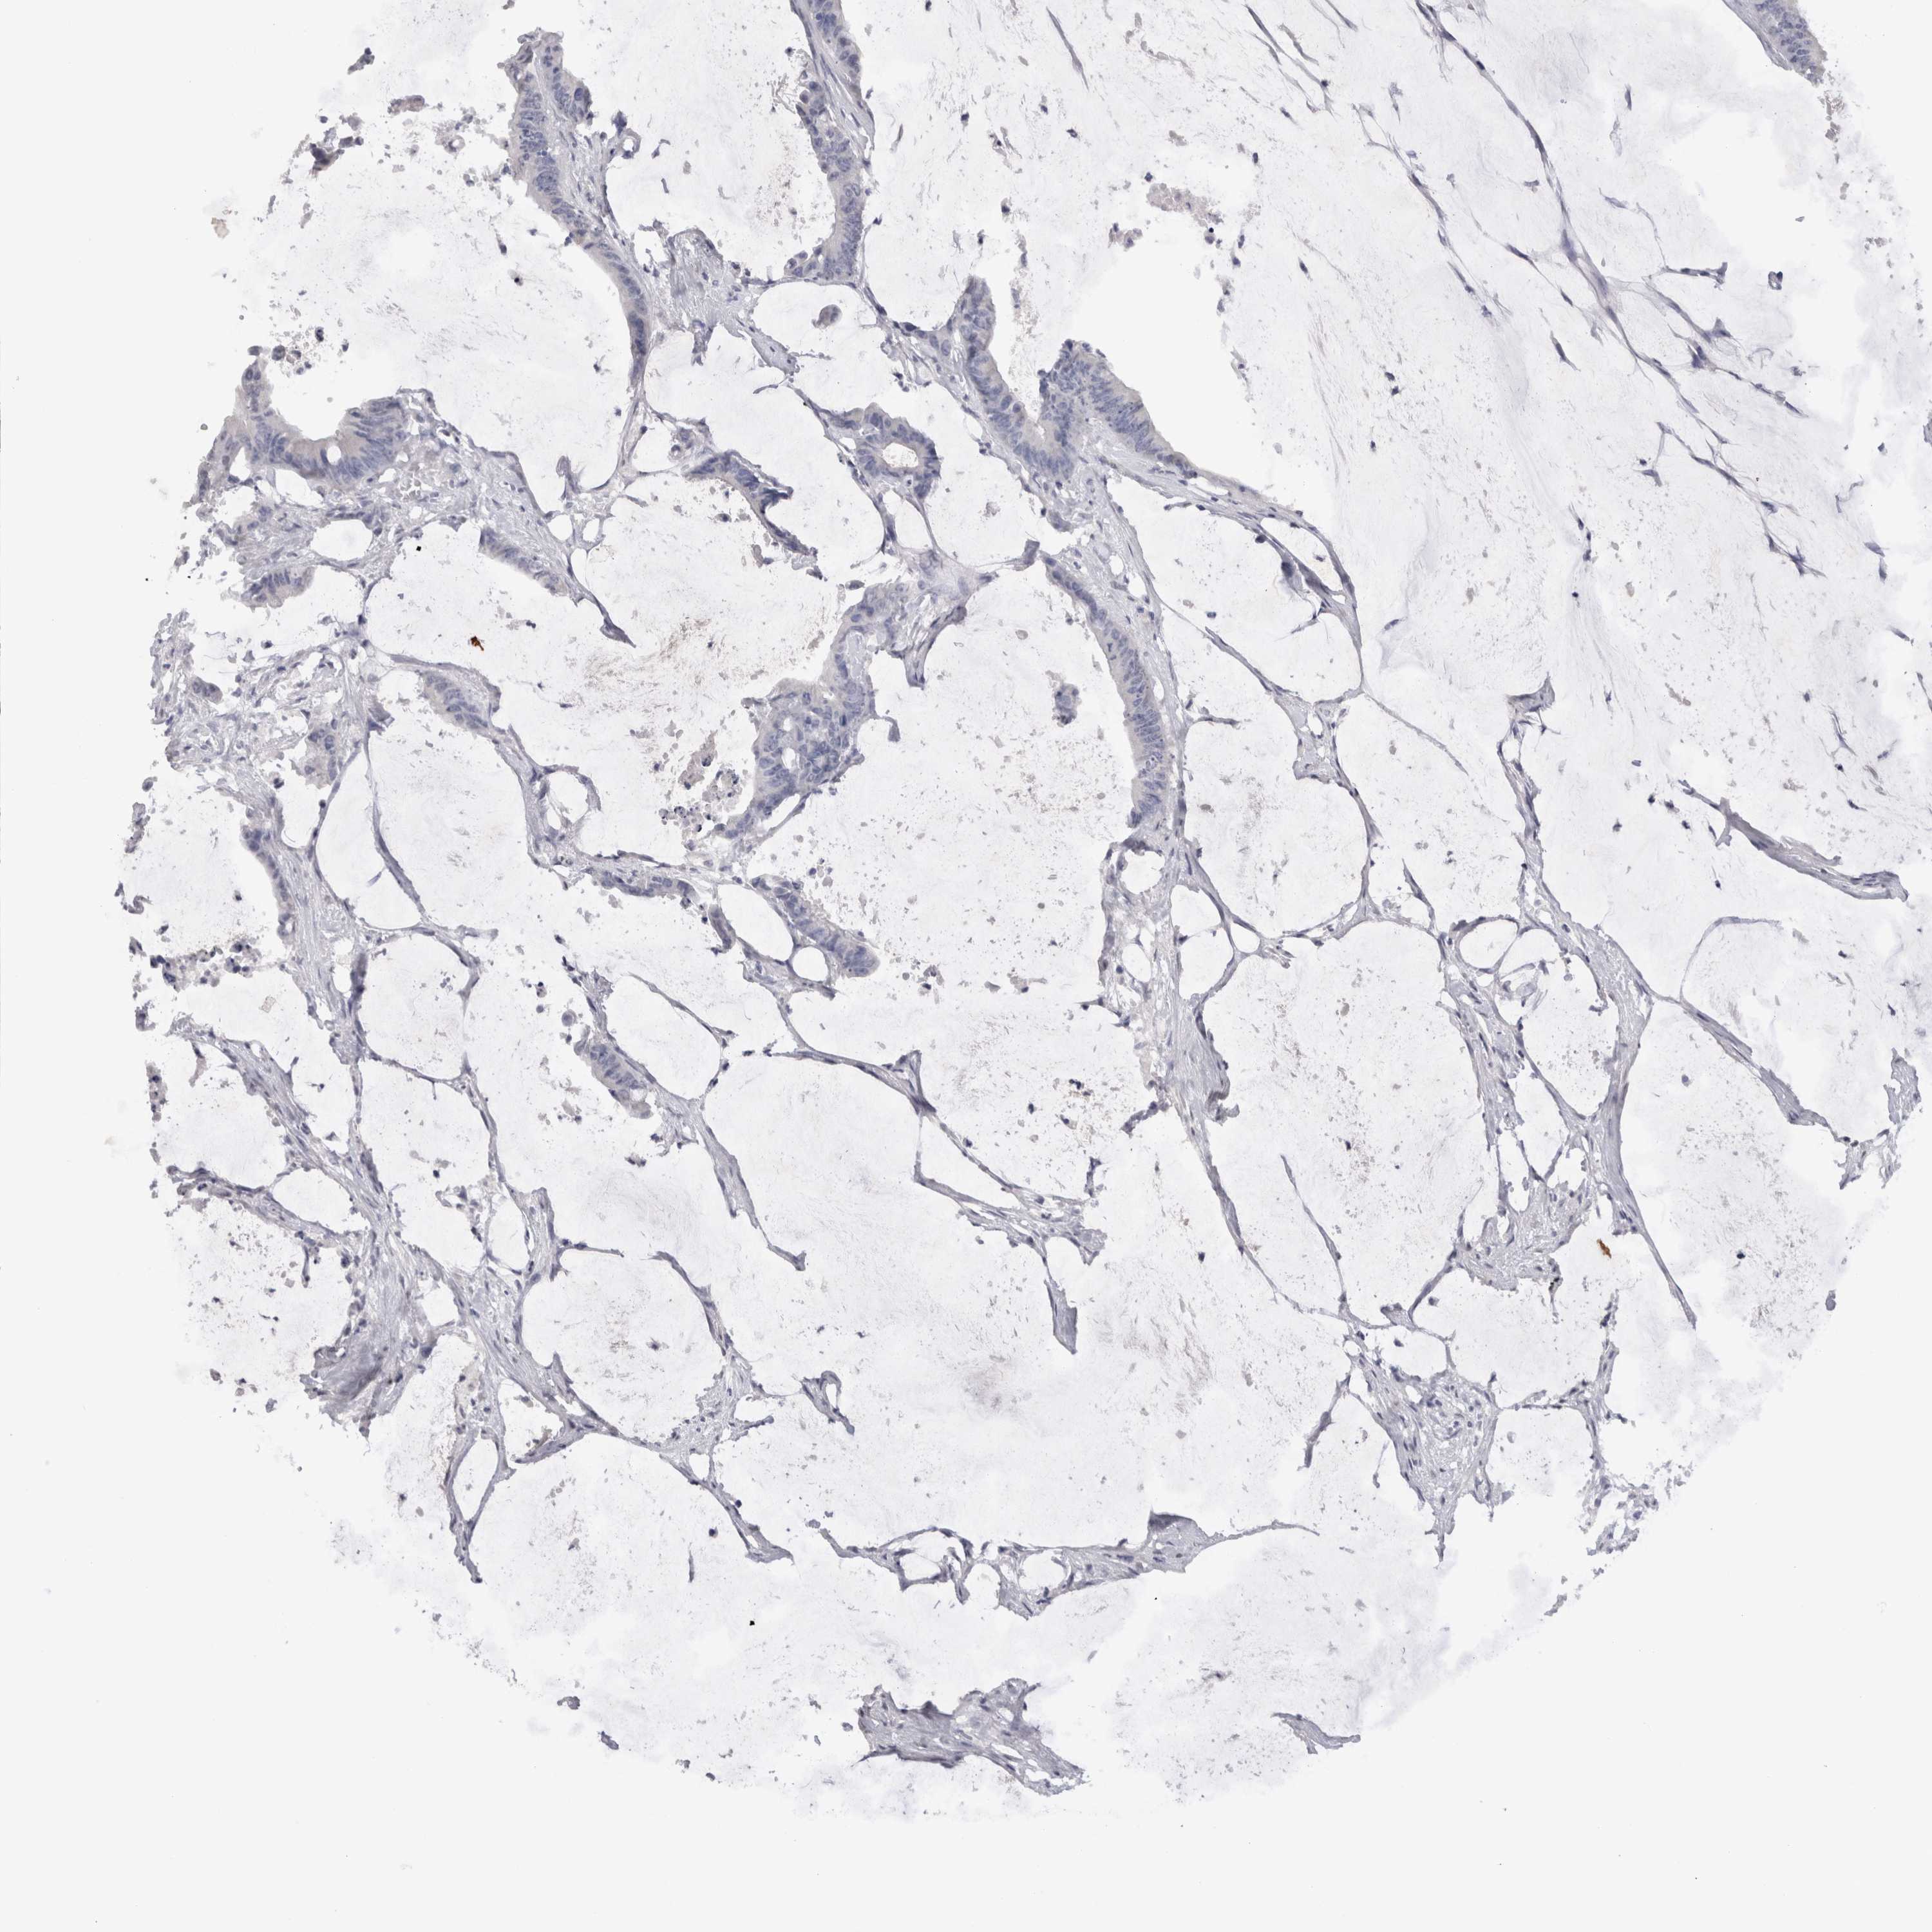

CANCER COLORECTAL CANCER Show tissue menu

Colorectal cancer

Human cancer

Colon adenocarcinoma